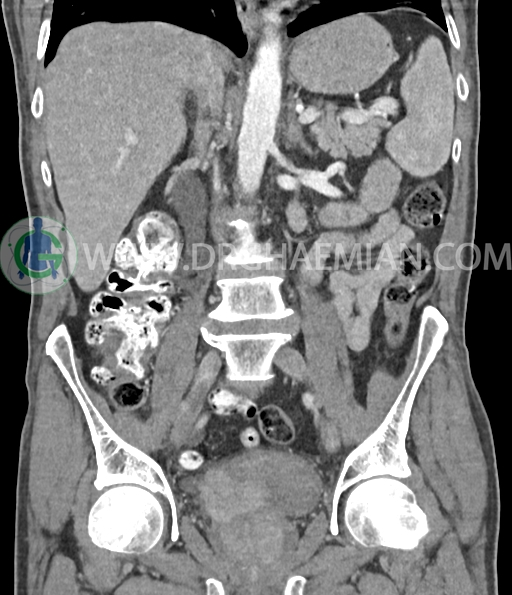

در سی تی اسکن اسپیرال شکم و لگن با و بدون کنتراست خوراکی و وریدی (مولتی دیدکتور 16 با مقاطع ظریف و بازسازی های ساژیتال و کرونال) :

دیورتیکولوز خفیف پراکنده بیشتر در کولون نزولی رویت شد.

افزایش ضخامت جداری و نامنظمی و لوبولاسیون همراه باenhancement مطرح کننده انفیلتراسیون و ضایعات تومورال در سمت راست ناحیه ترایگون و دیواره لترال راست مثانه دیده می شود که باعث اتساع حالب راست و هیدرونفروز moderate در کلیه راست شده است . این یافته های می توانند مطرح کننده TCC باشند .fat stranding در اطراف مثانه مشهود است. بیرون زدگی توده مانند به قطر 18mm در سمت راست ناحیه ترایگون دیده می شود که می تواند مطرح کننده گسترش اکسترا وزیکولر تومور باشد . لنفادنوپاتی با SAD=10mm درlevel ایلیاک داخلی چپ رویت شد . لنف نود دیگر با SAD= 5mm در همین ناحیه مشهود است. با توجه به این یافته ها stage احتمالی تومور T3، N1 or N2 می باشد .